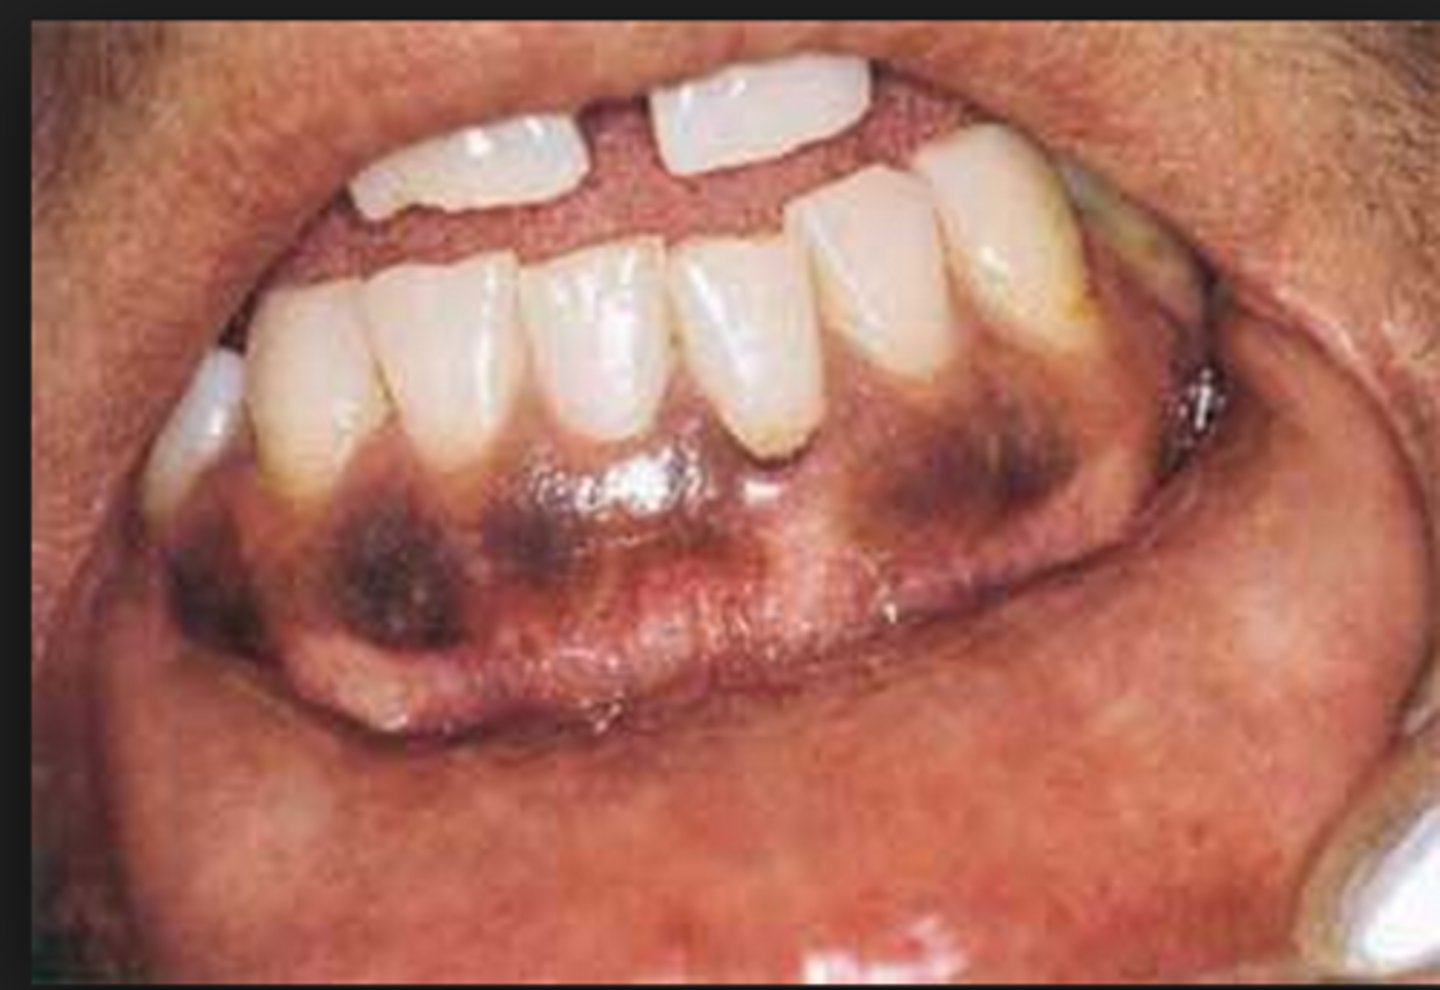

What is melanoma? (+ common locations)

blackish-blue, irregular papule

⢠poor prognosis

⢠common locations: palate, maxillary gingiva